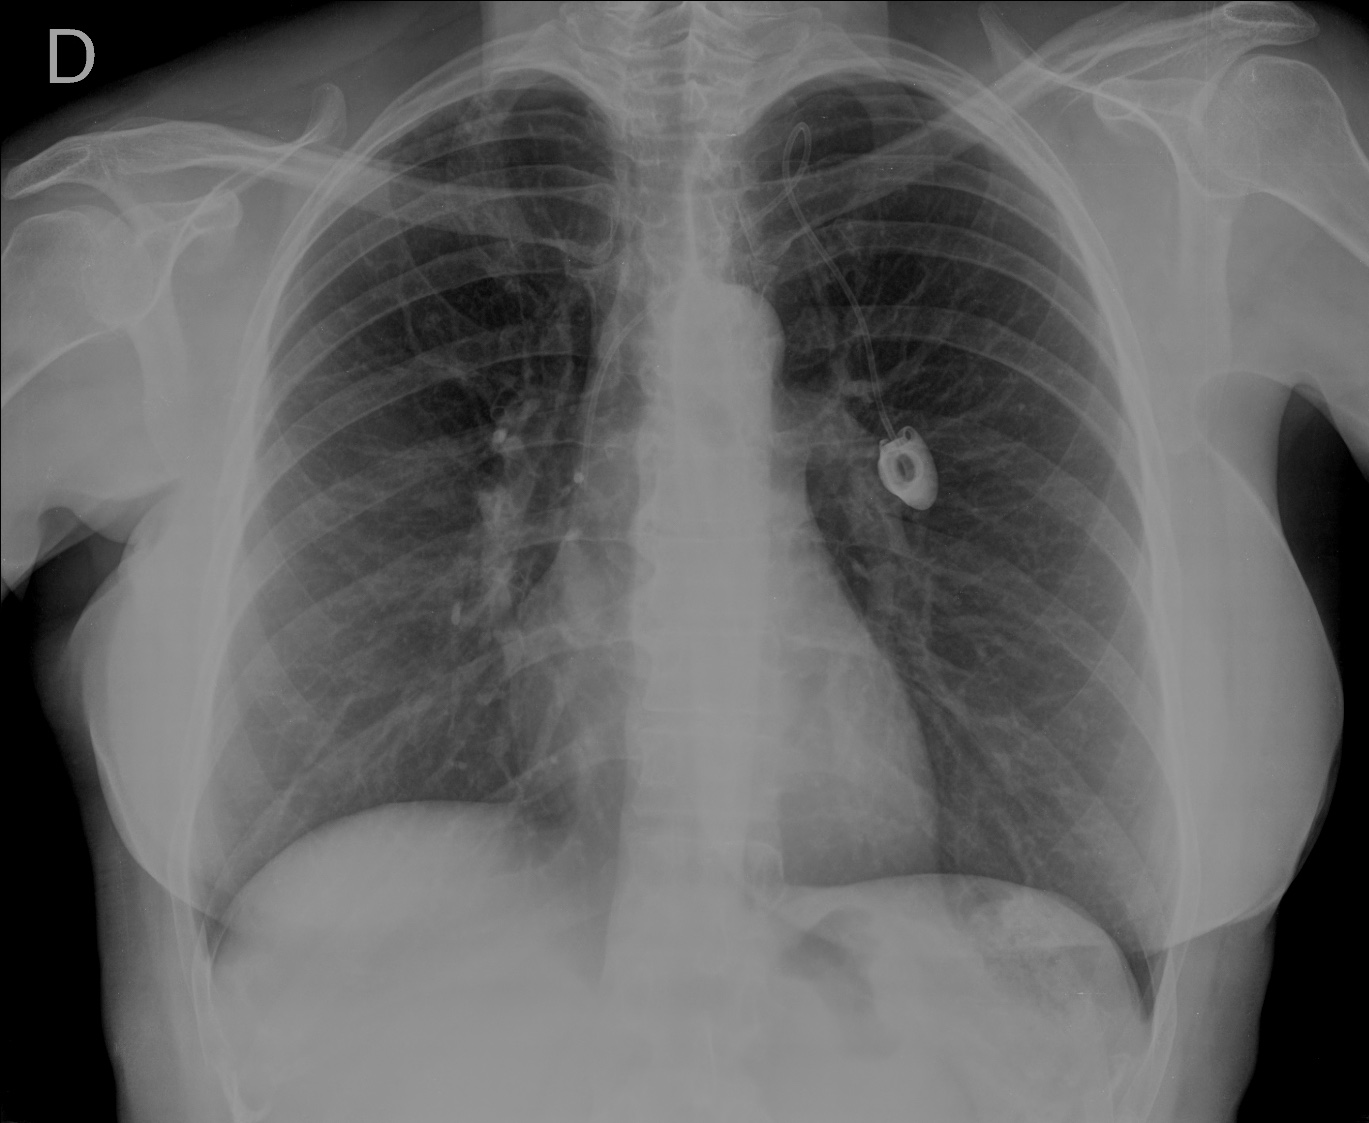

CASO: Operada de cáncer de mama izquierda en revisión.

Hallazgos:

- Prótesis mamaria izquierda (obsevar el aumento de densidad homogéneo y de bordes bien definidos en la placa PA y lateral)

- Parénquimas pulmonares y silueta cardiomediastínica sin alteraciones significativas.